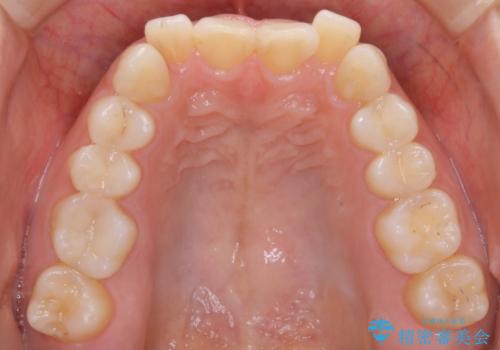

上顎の真ん中の歯の角度が、内側に傾いており、またその隣の歯が、唇側にずれてしまっていました。

上顎の前歯の傾きを改善することで、がたつきを治すためのスペースを確保しました。

また、それだけではがたつきを改善するスペースが不足していたため、歯の側面を削りがたつきを改善しました。